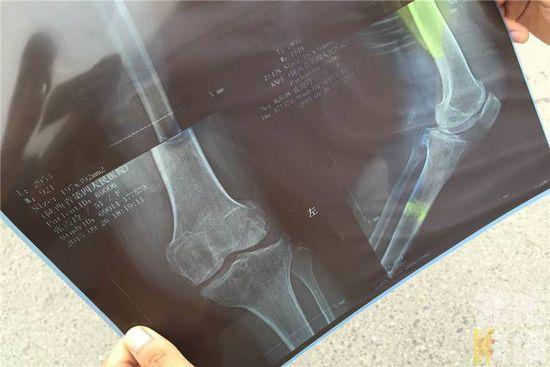

老太的家人赶到后,送医院,经过医生的诊断,受伤老太的腿部以及膝盖受伤严重,还需要做手术。